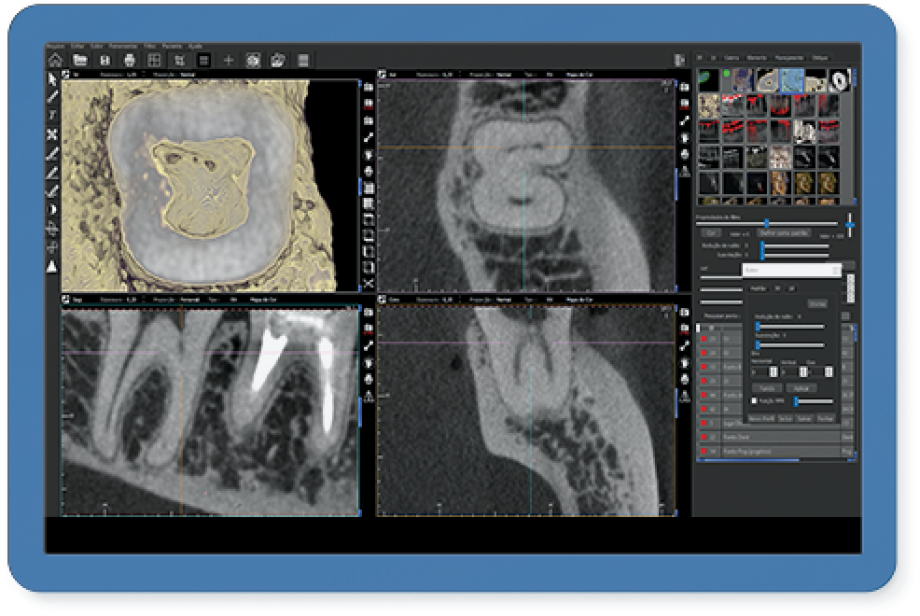

Entre os produtos oferecidos pela CDT Software é o E-VOL DX, reconhecido por pesquisas acadêmicas nacionais e internacionais de odontologia, possibilita imagens mais nítidas e com maior riqueza de detalhes! “O e-Vol DX é um software que supre demanda dos tradicionais aparelhos de radiologia. Compatível com os principais equipamentos do mercado, ele é composto por filtros e ferramentas que transformarão seus laudos”, ressalta.

Além disso, o e-Vol DX está em constante atualização para atender e antecipar-se às demandas dos profissionais da área de radiologia odontológica. Por isso, é um investimento seguro e eficaz e que não estará defasado. Com todos os recursos que garantem obter as melhores imagens de seu tomógrafo, o e-Vol DX possibilita otimizar o tempo de produção com o uso de ferramentas exclusivas.